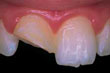

Chipped

Abgesplitterter Frontzahn